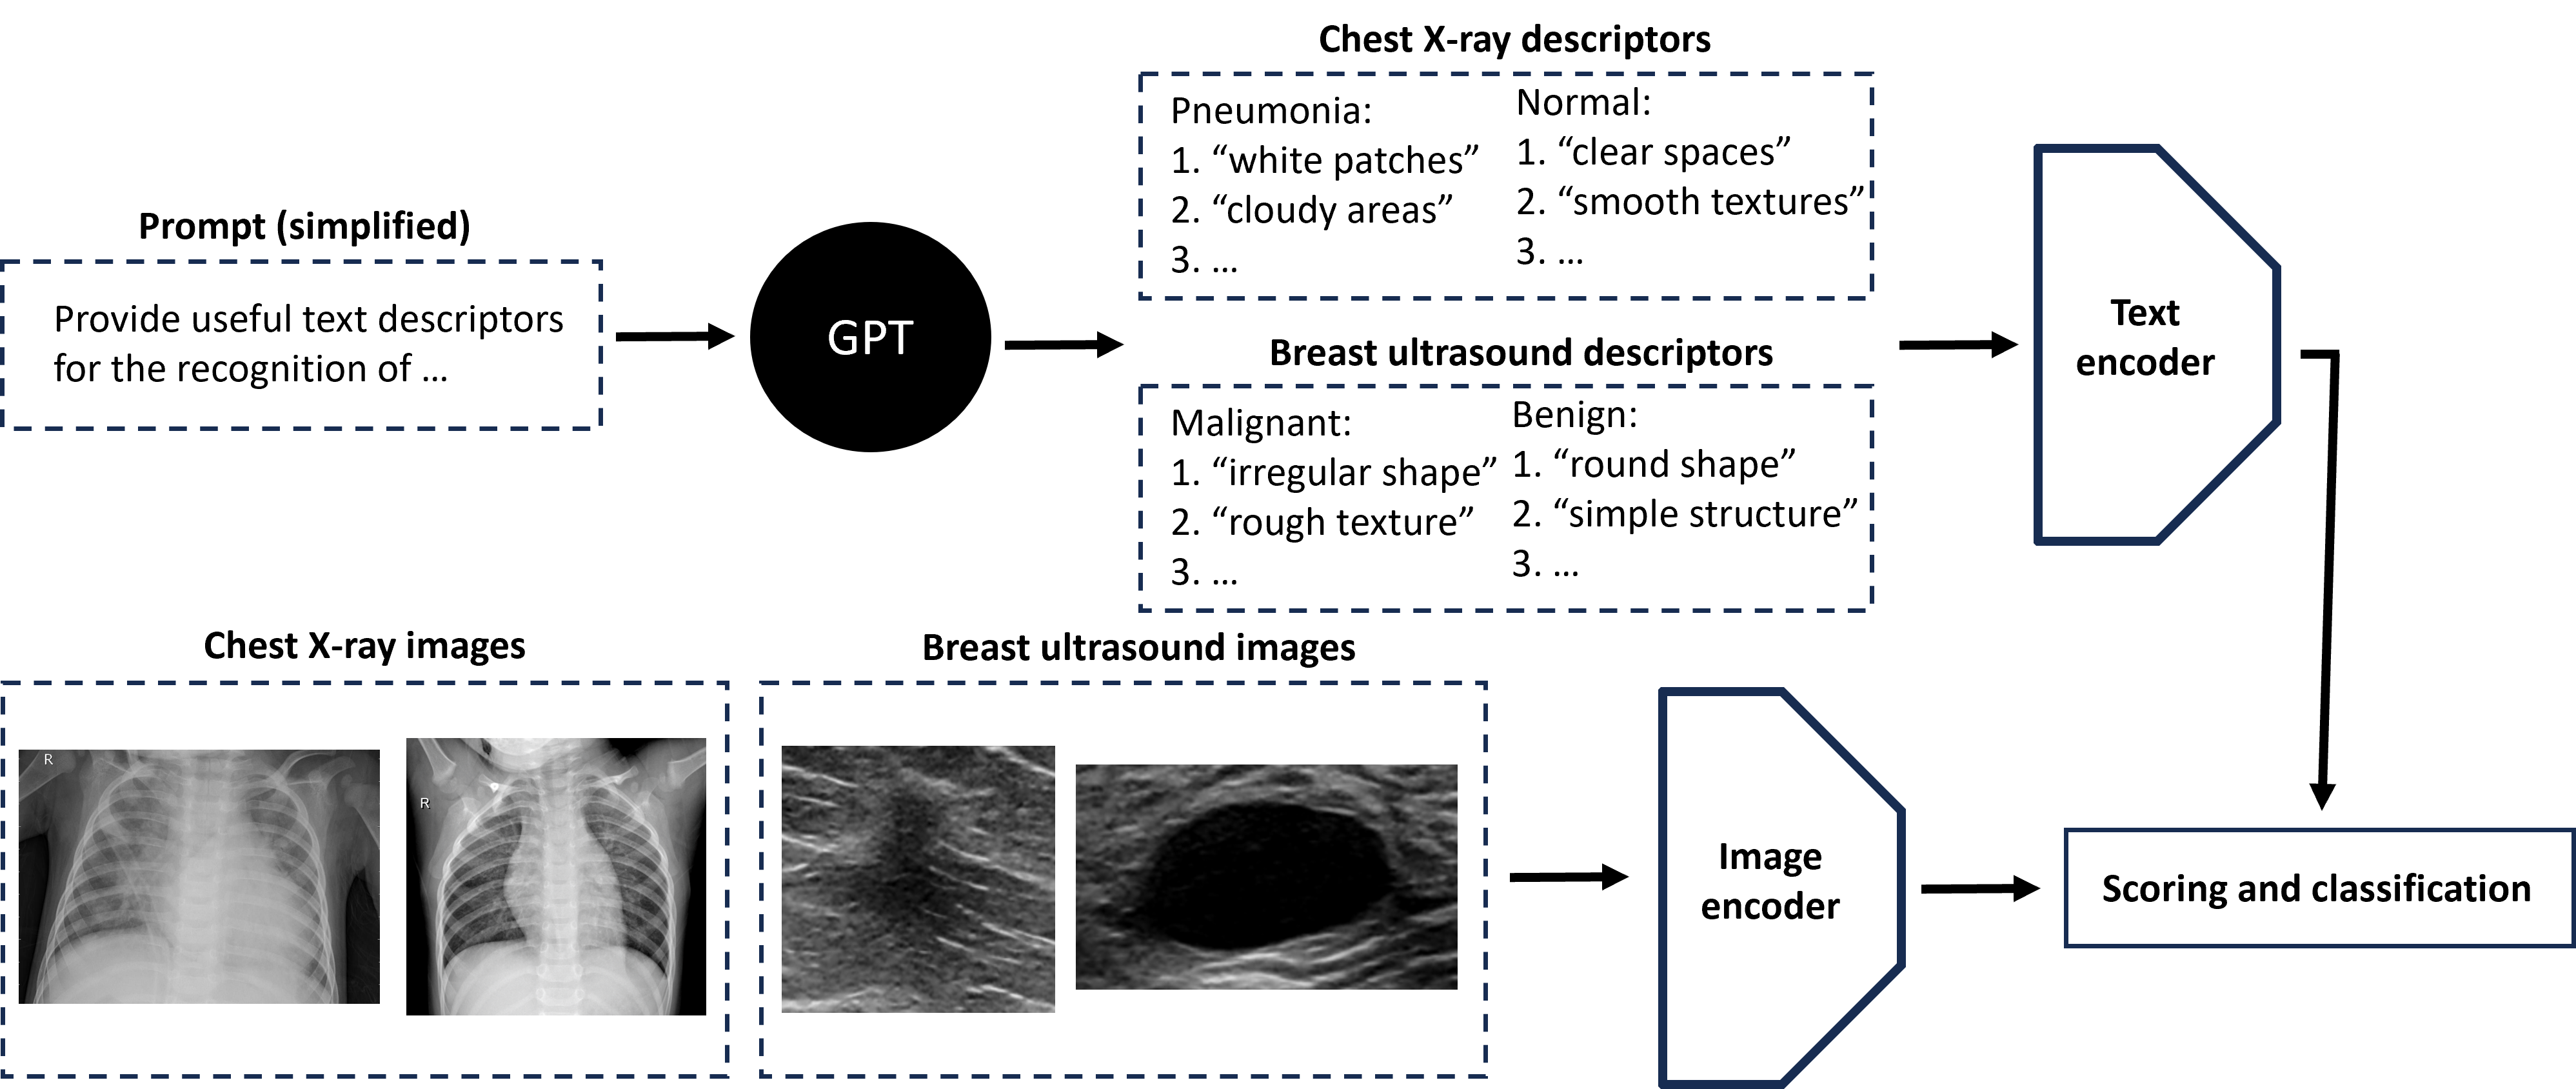

Figure 1 presents our approach to the few-shot classification of medical images. First, we used GPT-4 to generate suitable text descriptors for the particular classification task. GPT-4 was prompted to generate 20 simple descriptors related to shape and texture features. These descriptors should enable a VLM, pre-trained on natural images, to effectively handle medical images. A separate set of 20 text descriptors was generated for each class category. See Appendix A for the exemplary GPT-4 prompts and the generated text descriptors.

Refer to caption

Figure 1: Scheme presenting the proposed approach to few-shot medical image classification with vision-language models. GPT-4 was used to generate simple text descriptors related to the shape and texture of medical images.